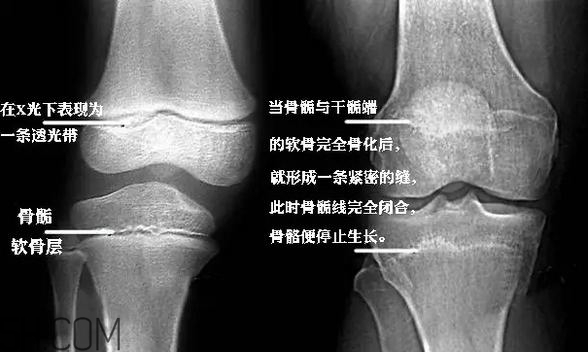

“骨骺”是兒童出生后在不同時(shí)間內(nèi)出現(xiàn)的二次骨化中心,通俗一點(diǎn)就是骨骼的生長(zhǎng)點(diǎn)。

適量的運(yùn)動(dòng)會(huì)刺激生長(zhǎng)點(diǎn),促進(jìn)孩子的生長(zhǎng)發(fā)育。

但是運(yùn)動(dòng)量過(guò)大時(shí),就會(huì)造成慢性疲勞,損傷到骨骺,就會(huì)影響到孩子的生長(zhǎng)發(fā)育了。